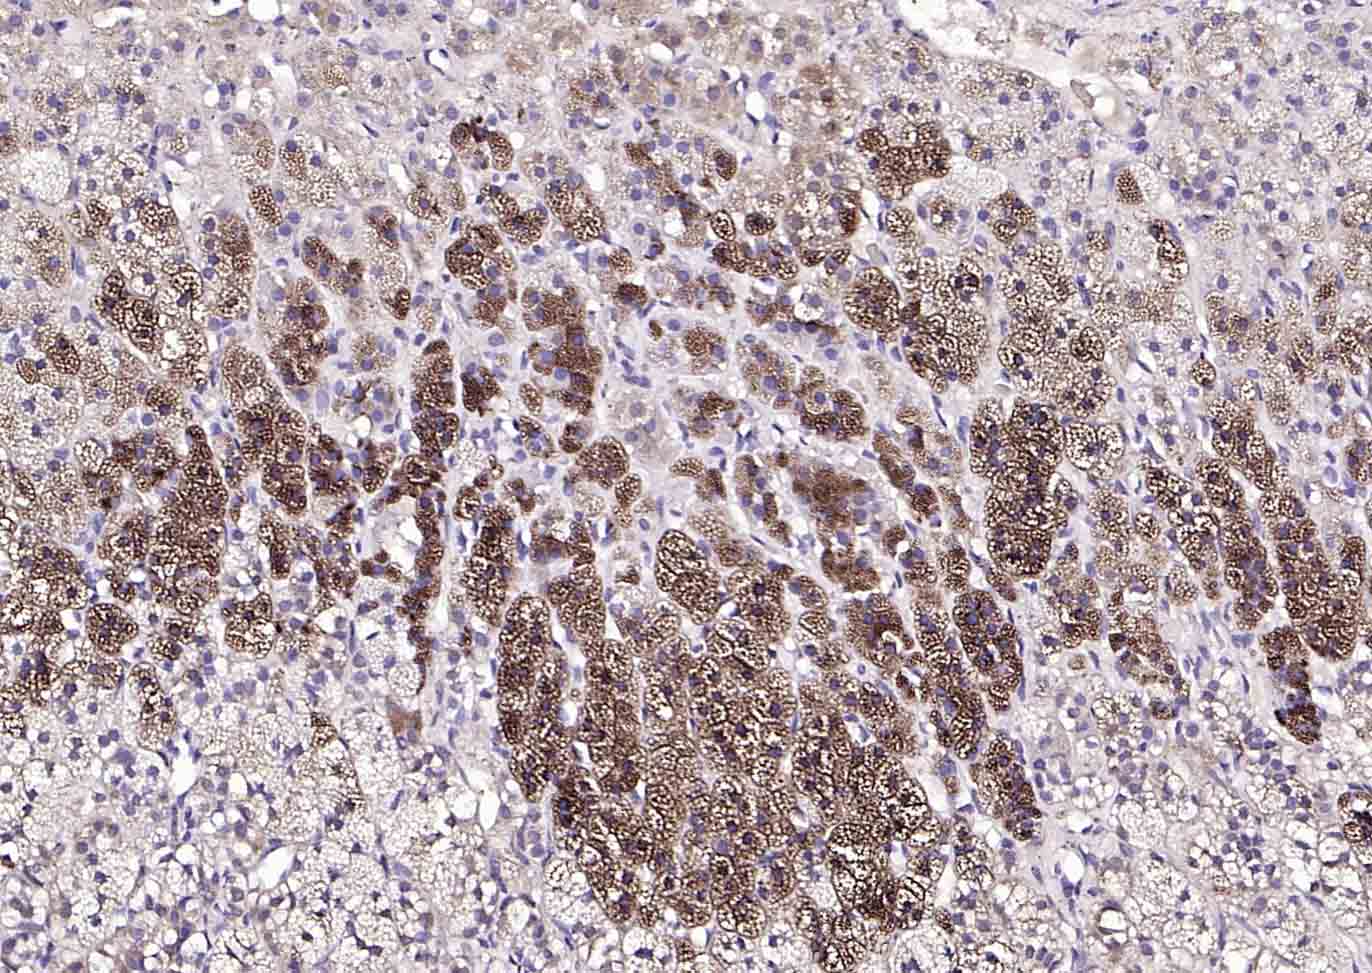

| IHC-P | Human, Mouse, Rat | Dog, Horse | 1:100-500 |